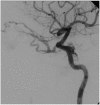

A carotid-cavernous fistula (CCF) is an abnormal communication between arteries and veins within the cavernous sinus and may be classified as either direct or dural. Direct CCFs are characterized by a direct connection between the internal carotid artery (ICA) and the cavernous sinus, whereas dural CCFs result from an indirect connection involving cavernous arterial branches and the cavernous sinus. Direct CCFs frequently are traumatic in origin and also may be caused by rupture of an ICA aneurysm within the cavernous sinus, Ehlers-Danlos syndrome type IV, or iatrogenic intervention. Causes of dural CCFs include hypertension, fibromuscular dysplasia, Ehlers-Danlos type IV, and dissection of the ICA. Evaluation of a suspected CCF often involves non-invasive imaging techniques, including standard tonometry, pneumotonometry, ultrasound, computed tomographic scanning and angiography, and/or magnetic resonance imaging and angiography, but the gold standard for classification and diagnosis remains digital subtraction angiography. When a direct CCF is confirmed, first-line treatment is endovascular intervention, which may be accomplished using detachable balloons, coils, liquid embolic agents, or a combination of these tools. As dural CCFs often resolve spontaneously, low-risk cases may be managed conservatively. When invasive treatment is warranted, endovascular intervention or stereotactic radiosurgery may be performed. Modern endovascular techniques offer the ability to successfully treat CCFs with a low morbidity and virtually no mortality.